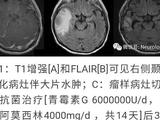

入院后予口服硫胺素(维生素B1)6mg/(kg·d)及左卡尼汀、辅酶Q10等,静脉滴注能量合剂、银杏叶提取物注射液(商品名:金纳多)及脱水剂,维持内环境稳定,治疗第3天患儿易激惹状态好转,哭闹减少,吃奶、睡眠逐渐恢复正常,住院10d复查头颅MRI显示双侧基底节区软化灶,其余异常信号范围略缩小(图2),住院12d出院。出院后基因检查回报,发现患儿SLC19A3基因纯合变异:chr2:228566898(c.137T>C,p.Leu46Pro),为错义变异,其父母该位点均为杂合子(图3),该变异可能导致THTR2蛋白质功能受到影响,其致病性尚未见文献报道[参考数据库:人类基因突变数据库(HGMDPro)及PubMed];线粒体基因检测未见异常。据基因结果及临床表型确诊生物素-硫胺素反应性基底节病(BTRBGD),予口服生物素3mg/(kg·d),硫胺素增至24ms/(kg·d)。患儿3月龄时因痉挛发作半个月再次入院,复查头颅MRI示双基底节软化灶、双侧丘脑区T1稍高信号(图2),复查BAEP正常、VEP双侧P100可引出,复查血乳酸正常,予口服托比酯、静脉滴注甲泼尼龙治疗,痉挛发作逐渐减少,住院2周出院。随诊到4月龄时,痉挛发作停止,患儿吸吮困难、肌张力增高。再次出院后随访半年,精神、运动发育仍落后,无抽搐发作,复查脑电图示背景慢波,可以见到多灶性痫性放电。